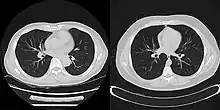

Example showing differences between filtered backprojection (right half) and iterative reconstruction method (left half)

CT scan using iterative reconstruction (left) versus filtered backprojection (right)